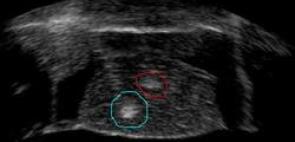

In this paper, a linear method is used for simulation, and the mass, spring and damper model is expressed. The HIFU simulator is used to measure HIFU, a phantom, as Figure 10 is considered. By putting the values of the mass, spring and damper in the simulation, pressure of HIFU on a tissue can be achieved, including a layer of the kidney.

Refer to caption

Figure 10: Figure of phantom intended for related software.